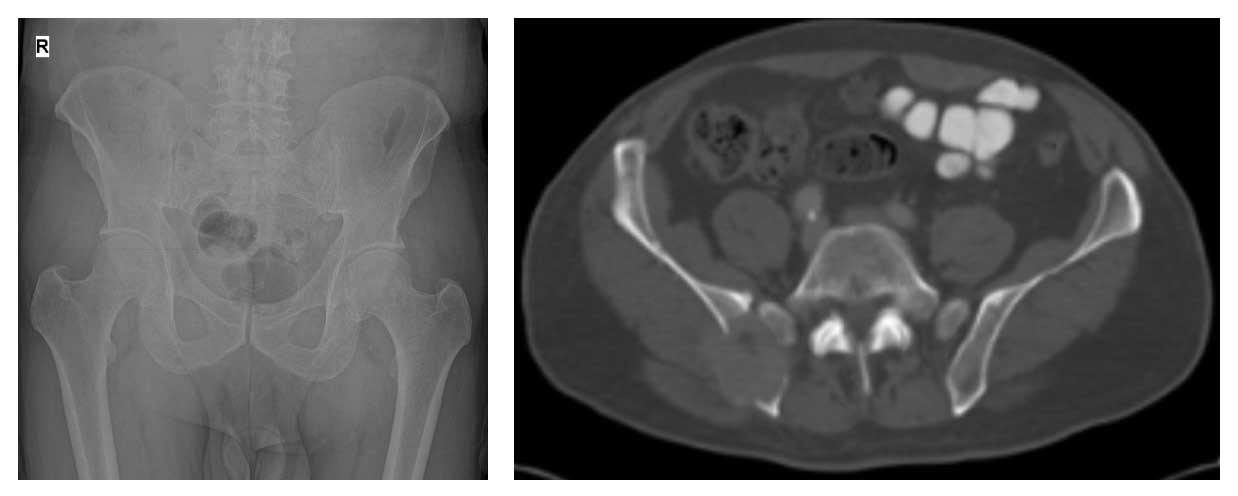

64 yaş erkek hasta. Tiroid kanseri nedeniyle daha önce ameliyat edilmiş ve radyoaktif iyot tedavisi uygulanmıştır. Son üç aydır sağ kalça arkasında giderek artan ağrı ve yürüme güçlüğü şikayetiyle başvurmuştur. Yapılan biyopsi sonucunda metastatik tiroid kanseri tanısı doğrulanmış, ek metastaz saptanmamıştır.

Ameliyat Öncesi: Röntgen ve tomografide sağ leğen kemiği arka kısımda kemik harabiyeti ve kemiğin dışına taşan tümör dokusu görülmekte.